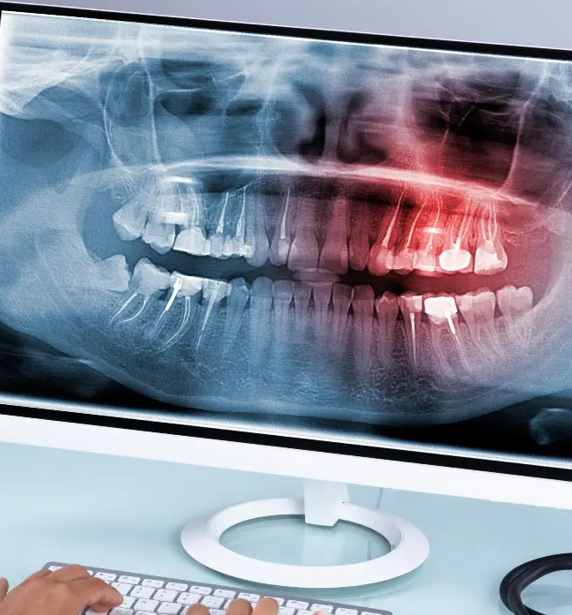

wisdom teeth in a dental xrayIf your wisdom teeth are causing you problems, our knowledgeable dentists are able to assist you with an assessment and the information required to provide a personalised treatment plan for the removal of one or more wisdom teeth.